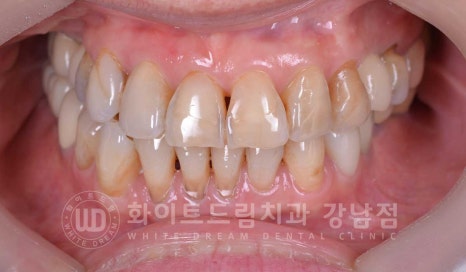

50대 여성분이셨고, 당일 빠르게 치료를 원하셔서

사전 예약 후 원 데이 라미네이트 진료를 진행하셨답니다.

환자분의 초진 구내 사진을 보면 앞니 부분에 마모가 심하게 진행되어 있는 상태입니다.

환자분의 미소라인을 보시면 상악만 노출이 되는 상태로 6개의 치아가 겉으로 보이는 상태입니다.

추가적으로 하악까지는 진행할 필요가 없어

상악 6개의 치아만 라미네이트 치료를 당일 진행하신 분입니다.

동일 인물이며 동일 환경에서 촬영됨

기간 : 24.06.25

노화된 치아 라미네이트

당일 잇몸성형을 진행한 후라 잇몸이 조금 부어있는 상태이지만

이는 5-7일 정도 시간이 지나면 자연스러운 원래의 잇몸으로 돌아오게 됩니다.